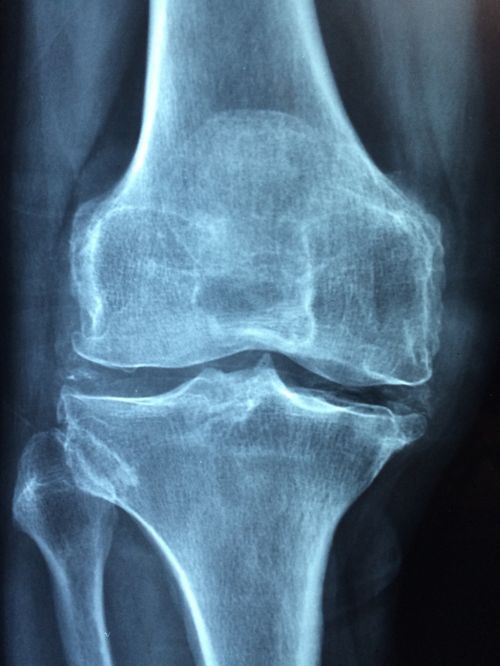

Врач спросит пациента о симптомах и проведет физическое обследование. Не существует окончательного теста, который может диагностировать остеоартрит, но тесты на визуализацию могут показать, произошло ли повреждение.

- Рентгеновские лучи: они могут обнаруживать костяные шпоры вокруг сустава или сужение пространства в суставе, что указывает на разрушение хряща;